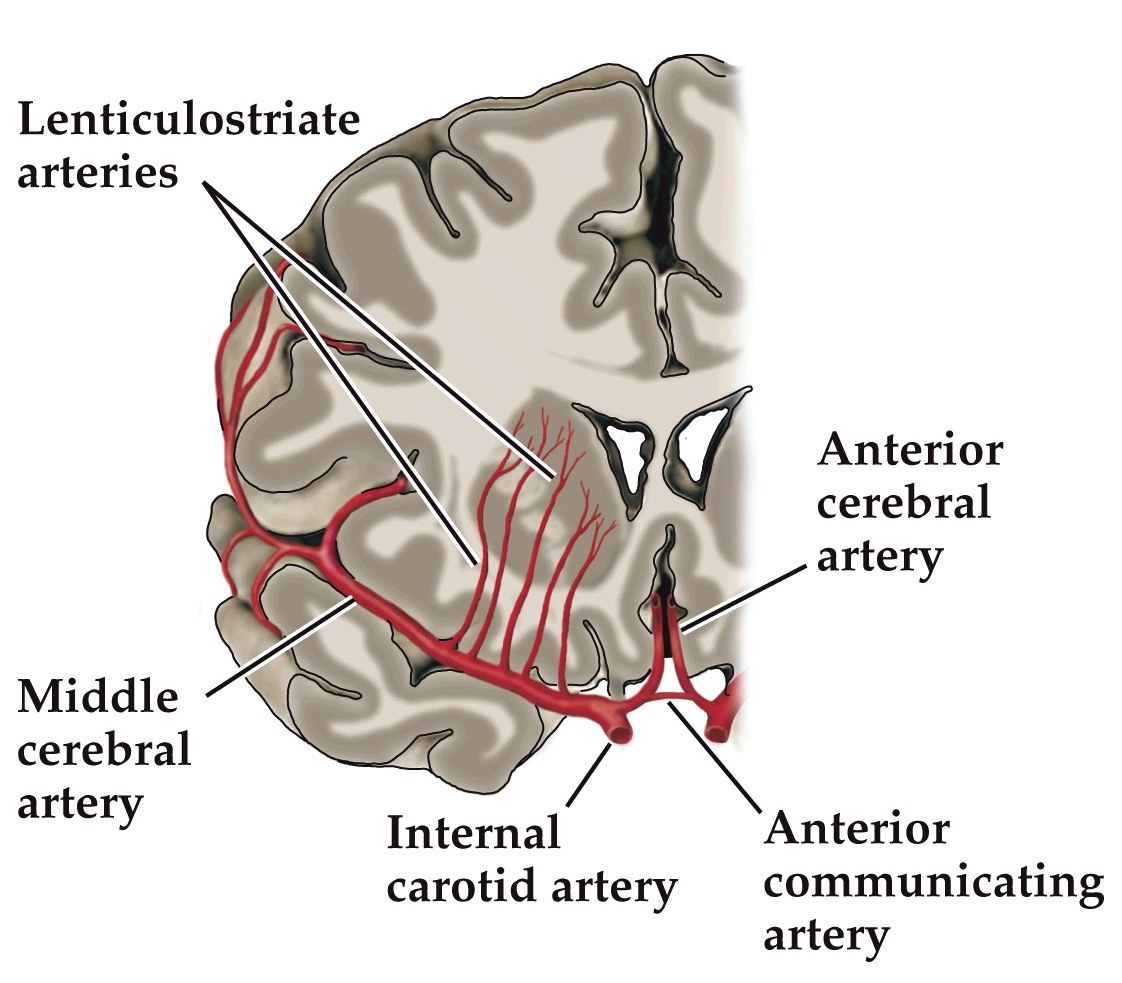

Cerebral circulation